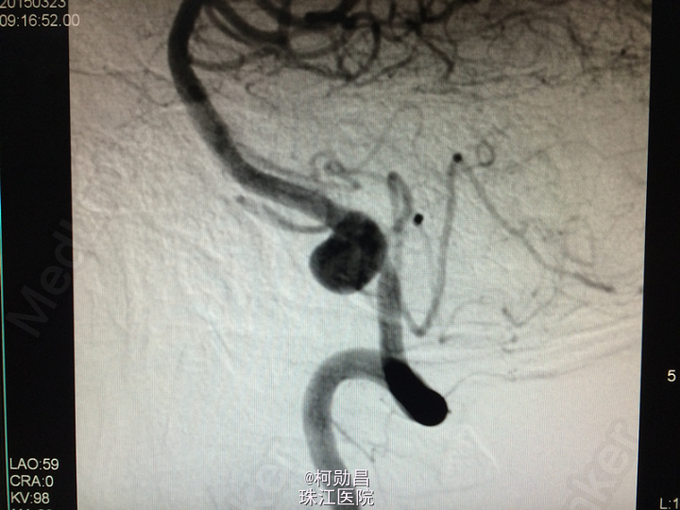

脑血管病入门级(3)-------LVA动脉瘤1例

患者49岁男性,因“头痛1个月,加重1周”入院,曾于2007年无明显诱因突发头痛、意识不清,行头颅CT检查示:蛛网膜下腔出血。于保守治疗后病情好转,未作进一步DSA检查等。入院前1个月患者再次出现头痛,左侧为主,呈爆炸样痛,无呕吐、意识障碍等。行头颅CTA检查提示:“左侧椎动脉动脉瘤”